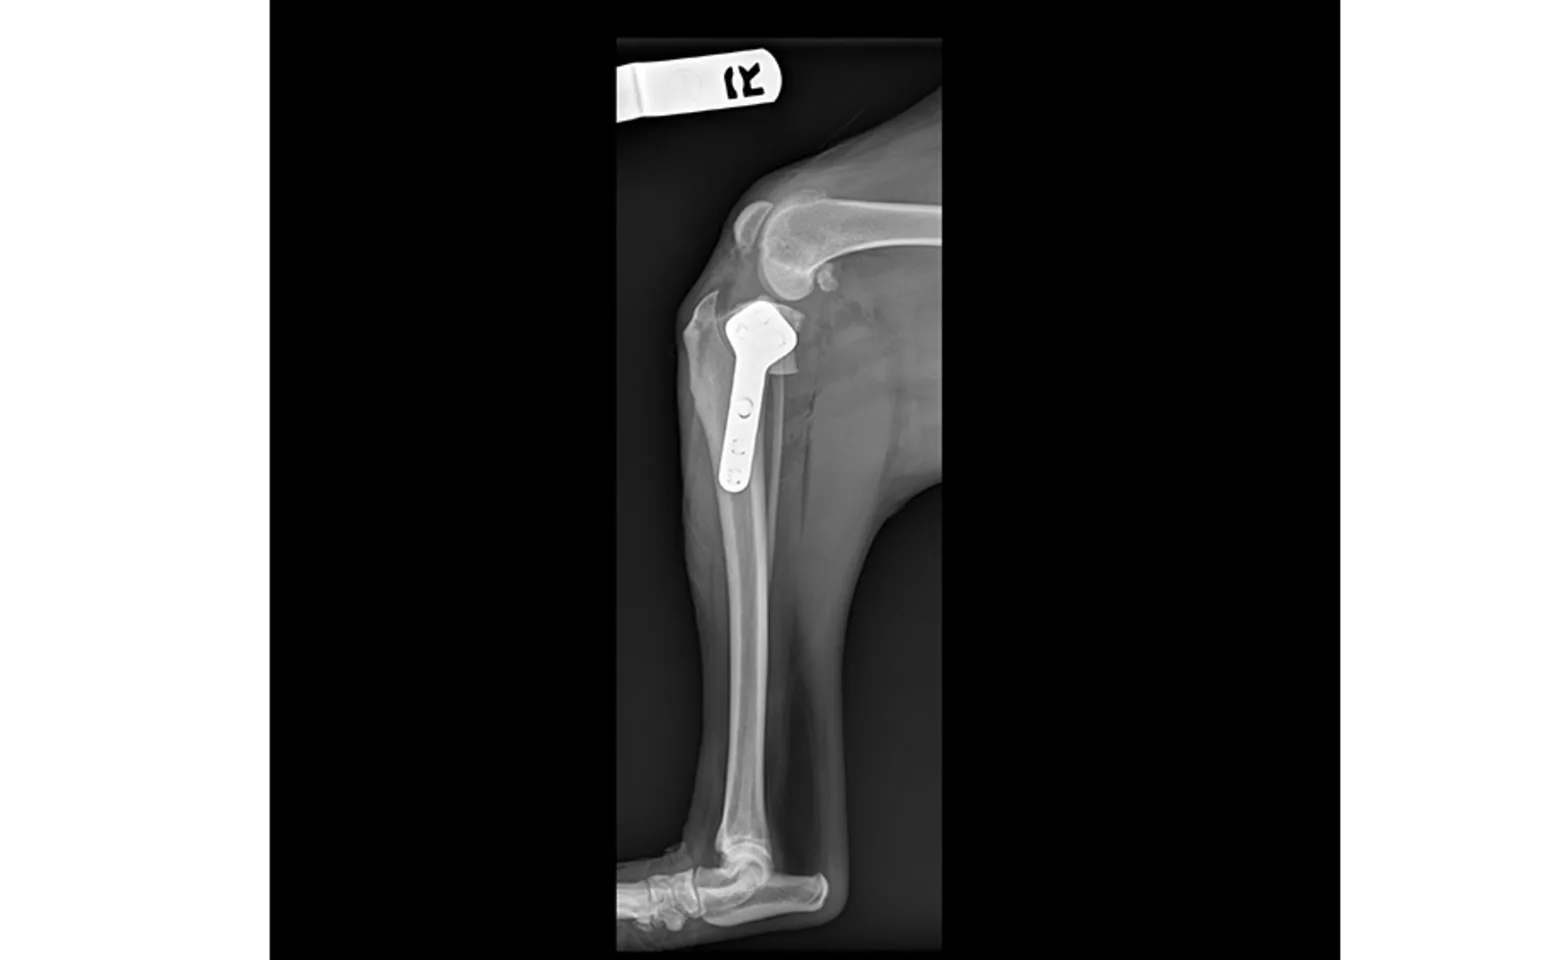

The TPLO surgery is performed by making a circular cut in the tibia and rotating the joint surface of the tibia so the forward and backward sliding, or tibial thrust, is neutralized. By changing the biomechanics of the joint in this fashion, the need for a CCL has been eliminated. The ligament is not replaced, as this has been shown to easily fail in canine patients. The cut in the bone is stabilized with a bone plate and screws. It is recommended that TPLO surgery always be performed by a specialized board-certified surgeon.